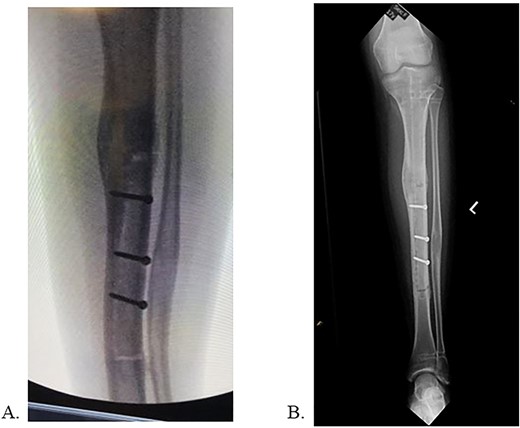

Final radiographs showed adequate alignment, internal fixation of the tibial osteotomy, and complete hardware removal aside from the three new fixation screws (Fig. 4A). The incisions were closed, dressed and the leg was immobilized in a Controlled Ankle Motion (CAM) boot. The patient spent six weeks non-weight bearing but was able to return to work without any pain or limping at three months post implant removal (Fig. 4B). Final 12-months follow-up demonstrated radiographically healed osteotomy site and maintained equal limb lengths and alignment (Fig. 5A-C).

A: 12 months postoperative PRECICE explantation with osseous union at osteotomy site of lateral left tibia. B: 12 months postoperative PRECICE explantation with osseous union at osteotomy site of AP left tibia. C: 12 months postoperative PRECICE explantation with equal limb lengths and alignment.